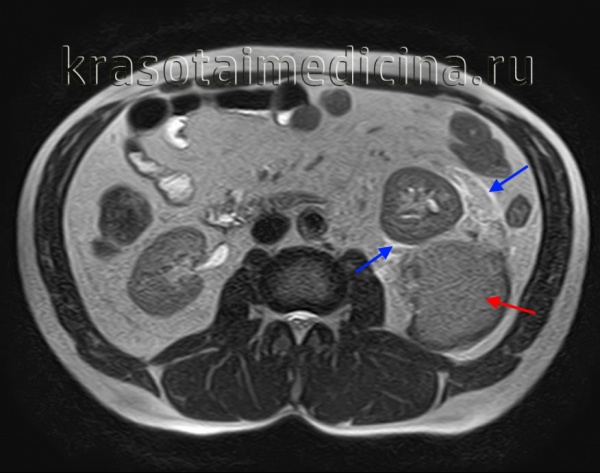

image

МРТ ОБП. Повреждение левой почки. Забрюшинная гематома (красная стрелка), отек перинефральной клетчатки (синяя стрелка).